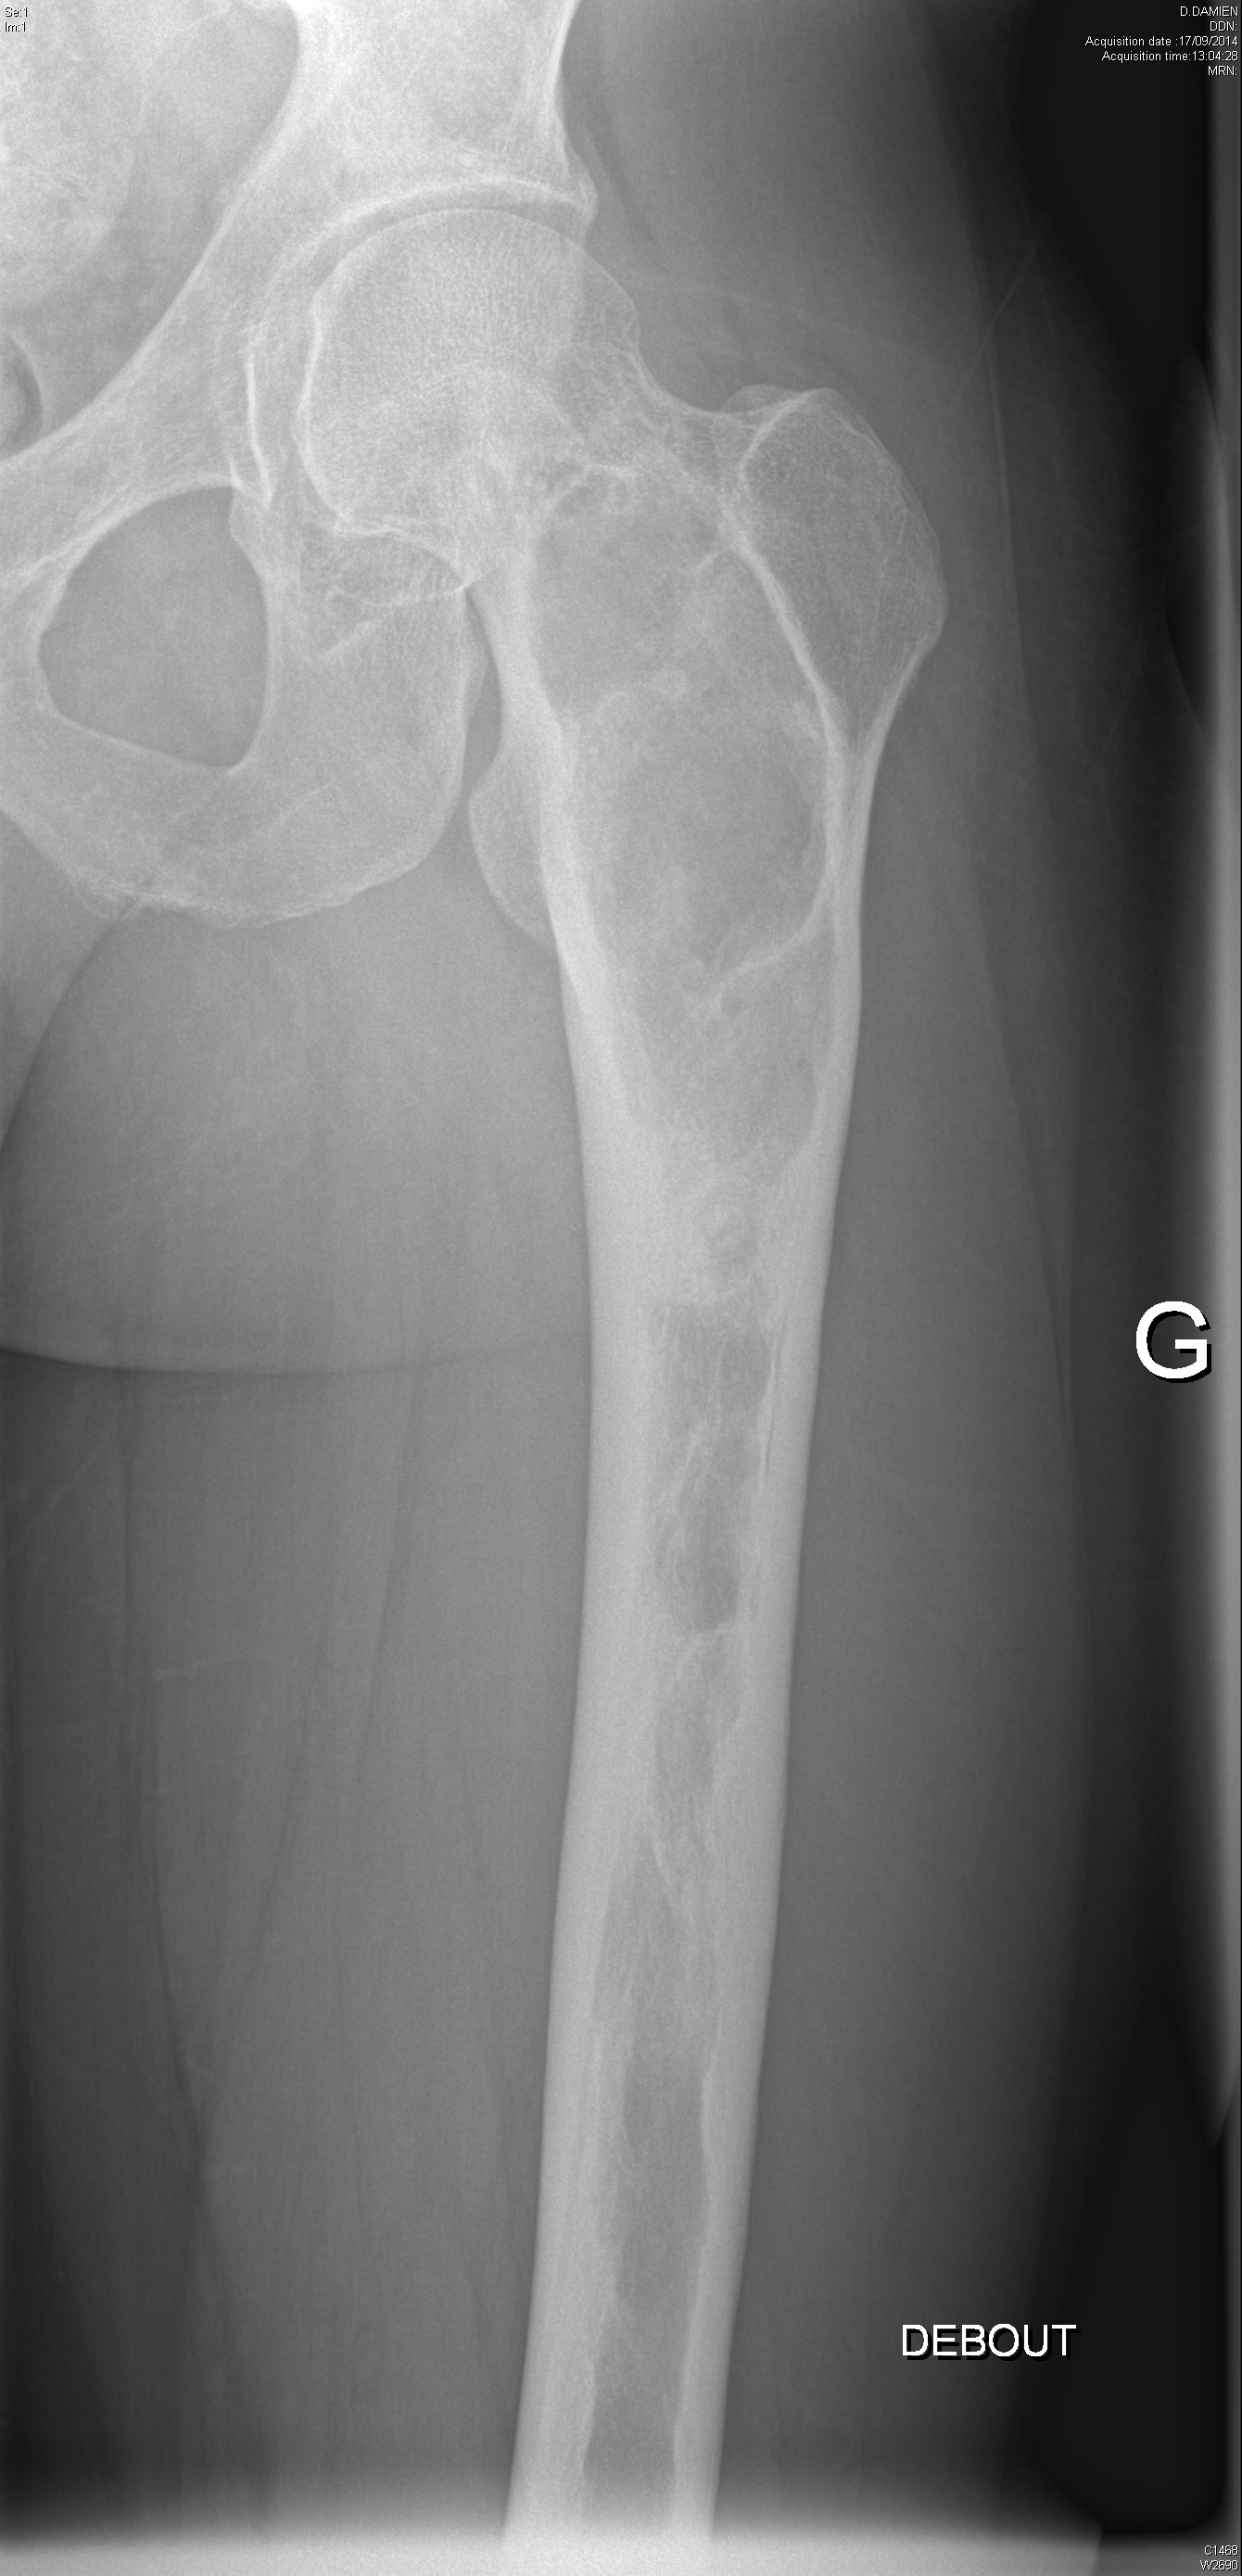

Dysplasie fibreuse du fémur gauche dans un contexte de dysplasie fibreuse polyostotique